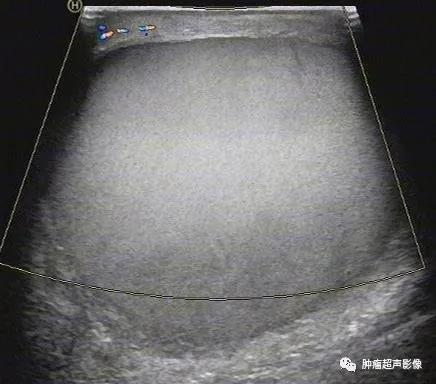

鞘膜积液术后,阴囊见中等回声,未见血流,这是一个发生病变的睾丸吗?

1、睾丸鞘膜腔积液:“三面环水”,阴囊内无回声区环绕睾丸三个面,只有一面靠岸。无回声区的大小取决于积液量,单纯性积液时其透声好,合并感染时内部可见点状回声、甚至分隔,外伤性积液无回声内部可见点状或团状回声,新鲜出血呈高回声(量大时呈椭圆形切勿认为是睾丸,需要仔细检查)。

睾丸鞘膜腔积液单纯性透声好,三面环绕睾丸